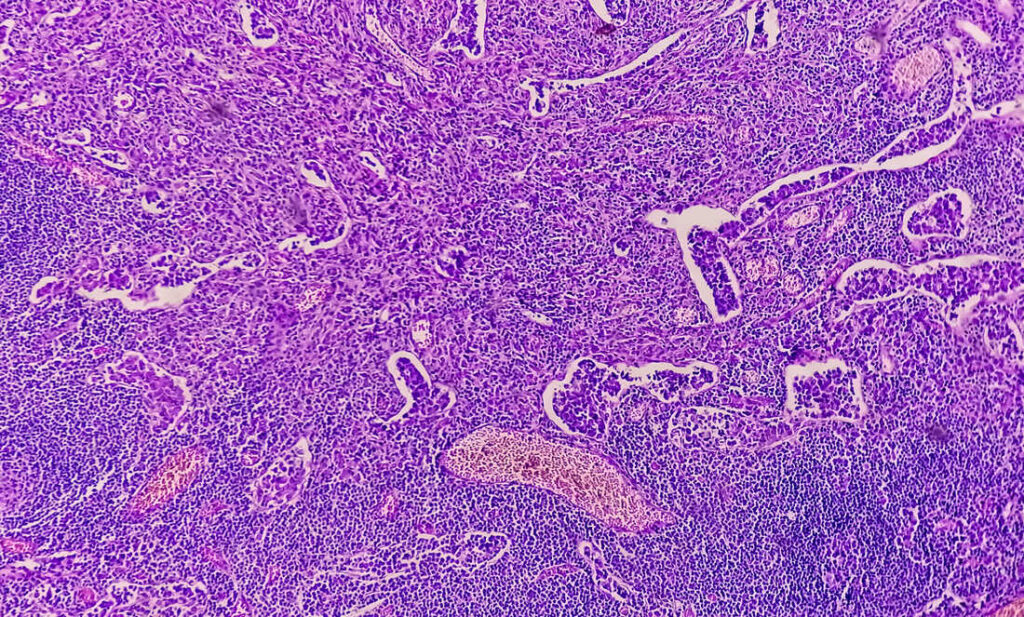

À l’aide d’un instrument optique introduit par la gorge, le médecin évalue l’état des voies digestives. En complément, il peut procéder à une biopsie, c’est-à-dire un prélèvement d’échantillons de la muqueuse. Ces échantillons seront ensuite analysés en laboratoire, et permettront de déterminer l’origine de l’inflammation.